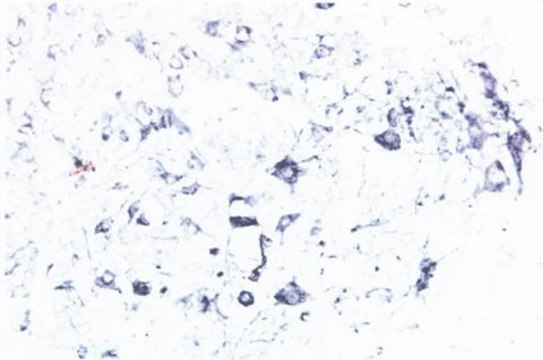

Immunohistochemistry: 1:2,000-1:3,000. The antibody reacts well with tissue from the rat spinal cord.